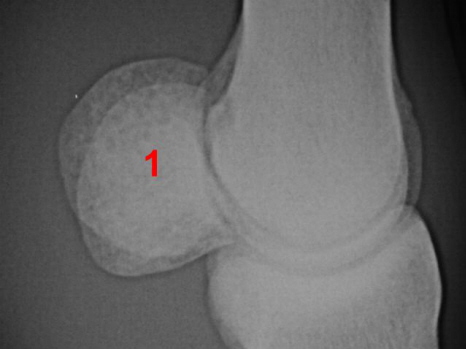

Gleichbeinentzündung